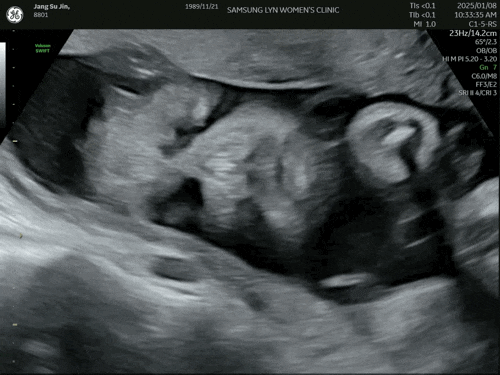

임신 26주, 27주차 - 일상, 2024 바이, 2025 시작, 성남사랑상품권 충전, 시댁식사, 태아검진휴가, 삼성린산부인과, 27주차 초음파

연말. 너무 안막혀 회사 너무 일찍 도착해감. 해가 안뜸.. 우리만 출근하넹.. D-100 !!! 세자리수 깨집니...

고구미!! 맛있는데 먹을때마다 코코 눈치봐야함ㅋㅋ 요염해라~ 병원가는날! 코코이찌방야 가서 카레 푸파!!...